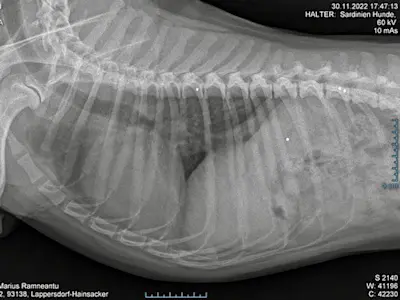

Unser süßer Lorenzo hat 2022 in Bayern sein endgültiges Zuhause gefunden. Es geht ihm sehr gut, die Leishmaniose-Therapie mit Allopurinol und Letifend war ein voller Erfolg. Er lebt in einem Haushalt mit 5 weiteren Hunden und ist bestens integriert. Er liebt seine Gassigänge und er liebt das Meer - wenn es denn nicht zu aufgewühlt ist. Bei einem Tierarztbesuch wurde eher zufällig entdeckt, dass Lorenzo eine ganze Ladung Schrotkugeln im Körper hat - man mag sich nicht vorstellen, was der kleine Kerl schon alles durchgemacht hat.

Die unter Narkose angefertigten Röntgenbilder brachten es dann ans Licht....eine deutliche HD macht ihm das Leben schwer. Da Lorenzo für eine Femurkopfresektion noch zu jung und die HD auch noch nicht extrem weit fortgeschritten ist versuchen wir nun, ihm mit einer PRP (plättchenreiches Plasma) Erleichterung zu verschaffen. Sollten die dafür notwendigen 3 Behandlungen nicht anschlagen, steht als Alternative eine Hyaluron Injektion ins Gelenk auf dem Plan. Als wäre der arme Tropf mit seiner Leishmaniose noch nicht genug geplagt – auch hier steht im April noch erneut die Kontrolle der aussagekräftigen Blutwerte auf dem Plan.